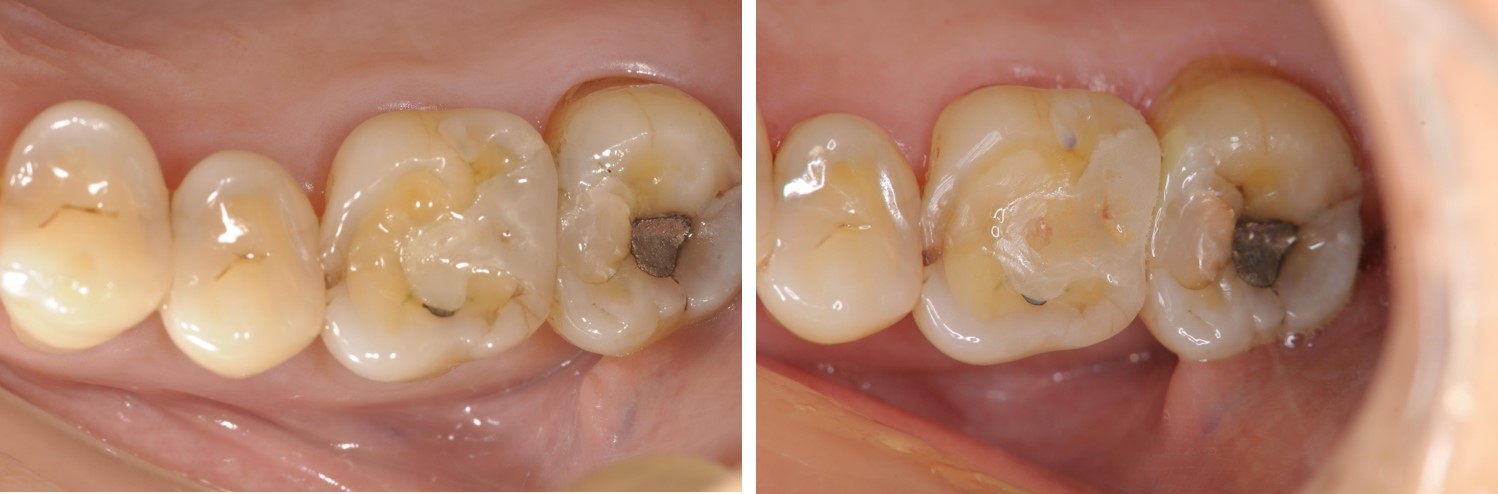

術前、術後比較